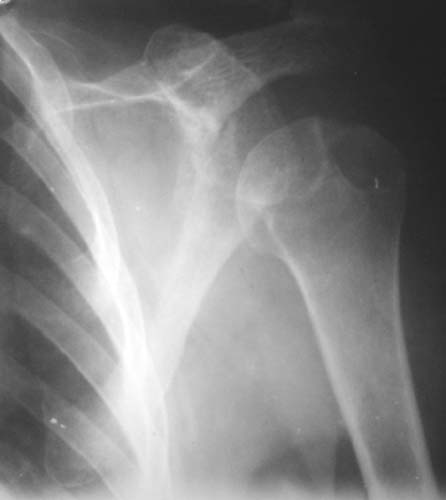

Уважаемые коллеги!Женщина, 60 лет. 3 недели назад упала с упором на отведенную левую руку. Почувствовала боль в левом плечевом суставе. За помощью не обращалась. 2 недели "мази и припарки". Затем - рентгенограмма (r1 и r2), жалобы на боли,ограничение движений...

Как Вам известно, в некоторых случаях вывихи плеча сопровождаются разрывом ротаторной манжетки, отрывному перелому большого бугорка что приводит к потере наружной ротации и отведения плеча. На представленных рентгенограммах перелом не виден.

МРТ должен показать разрыв манжетки, но признаться я не большой эксперт по чтению МРТ сканов, хотя затемнение, отек мягких тканей по задней поверхности плеча видны Обычные рентгенограммы демонстрируют остеолизис в области большого бугорка.

1. На рентгене - нижний подвывих плеча и очаг остеолиза суставного бугорка с четкими контурами (вдавленный перелом на фоне остеопороза ? доброкачественная опухоль? аваскулярный некроз ? (хотя ни разу не слышал об аваскулярном некрозе плеча..)

Судя по снимкам, речь идTт о типичном случае Hill-Sachs Lesion. По этому поводу я позволю себе некоторый экскурс:

97 % всех вывихов плеча происходит по механизму комбинации отведения, разгибания и наружной ротации (А. Гринспан). В момент вывиха головка плеча ударяет о нижний край гленоида, что ведет к вдавленному или компрессионному перелому одной или обеих структур. Чаще всего, однако, повреждение возникает в задней латеральной области головки плечевой кости на переходе от головки к шейке. Этот диагноз можно выставить на основании рентгеновского снимка в переднезадней проекции с внутренней ротацией плеча. Несколько реже видно повреждение гленоида о передненижний перелом края. То, что мы называем Bankart Lesion. Это повреждение видно на ре. снимке в п.з. проекции при нейтральной позиции плеча. Разумеется хрящевые и мягкотканные повреждения (в смысле Банкарт) мы увидим лучше всего на ЯМР.